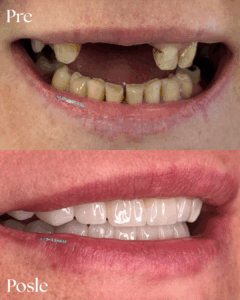

In Dental – Galleria

Rad1